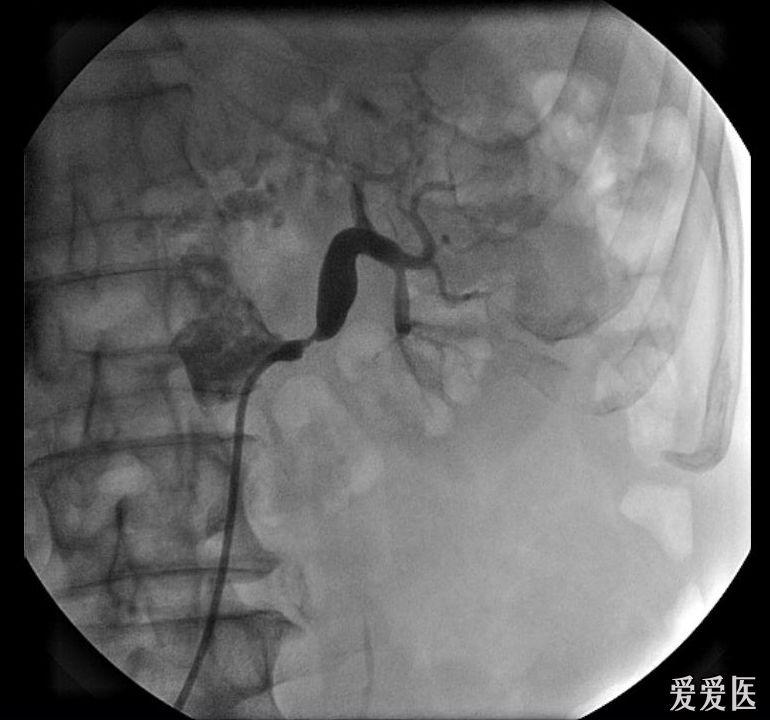

血管造影显示左肾动脉开口重度狭窄

肾动脉造影示右肾动脉主干狭窄

肾动脉狭窄造影表现